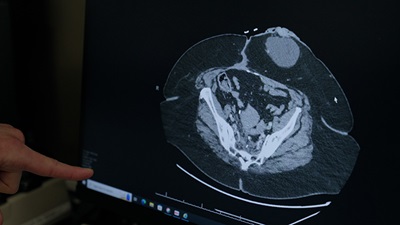

scan of colorectal cancerMetastatic colorectal cancer is cancer in the colon or rectum that has spread to other parts of your body. The most common places for colorectal cancer to spread are the liver, lungs, peritoneum and distant lymph nodes.